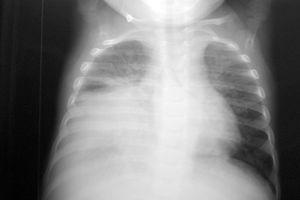

El paciente presentaba una coagulopatía que requirió tratamiento con plasma fresco congelado y vitamina K, así como anemia de 8 g/dl de hemoglobina (Hg) que requirió transfusión de concentrados de hematíes. La función respiratoria fue empeorando progresivamente, presentando presiones altas en la vía aérea (pico de 45-50 cm H2O, meseta de 19 cm H2O, compliance dinámica de 3,4 ml/cm de H2O y estática de 12 ml/cm H2O). Se asoció NO2 hasta 30 ppm al tratamiento. Tras aumentar progresivamente la presión positiva al final de la espiración (PEEP) hasta 7 cm H2O, el pulmón derecho aparecía más aireado, y tras la resolución del componente atelectásico que estaba asociado a la neumonía (fig. 1) se apreciaron dos imágenes compatibles con abscesos o bullas en el pulmón derecho (fig. 2). La evolución posterior fue hacia un síndrome de distrés respiratorio agudo (fig. 3). Se inició tratamiento con ventilación de alta frecuencia con una mejoría inicial de la oxigenación que no se mantuvo posteriormente.

Figura 3. Síndrome de distrés respiratorio agudo.